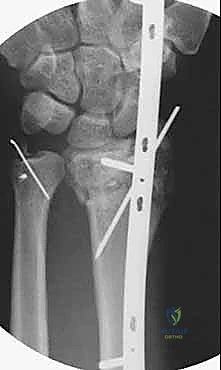

| الصفيحة الجسرية (Bridge Plating) | صفيحة طويلة تمتد من الساعد وتعبر المفصل لتثبت في عظام اليد. | الكسور شديدة التفتت، فقدان العظم، والإصابات المتعددة. | يتطلب جراحة ثانية لإزالة الصفيحة بعد التئام العظم (بعد 3-4 أشهر). |

مبدأ عمل الصفيحة الجسرية (Distraction Ligamentotaxis)

تعتمد هذه التقنية المتقدمة على مبدأ إبقاء المفصل مشدوداً ومثبتاً من الخارج. الصفيحة تعمل كـ "جسر" يعبر فوق منطقة الدمار الشامل في العظم، وترتكز على عظم سليم في الساعد وعظم سليم في اليد. هذا الجسر يمنع العظم المفتت من الانهيار ويسمح للشظايا الصغيرة بالالتئام في مكانها الصحيح بفضل الشد الطبيعي للأربطة المحيطة.

3. إدخال الصفيحة الجسرية (Plate Insertion)

بمهارة فائقة، يتم تمرير الصفيحة المعدنية المصنوعة من التيتانيوم تحت الجلد وفوق الأوتار عبر الشقين، بحيث تعبر مفصل الرسغ بالكامل متجاوزة منطقة الكسر المفتتة دون العبث بها.

5. وضع البراغي النهائية (Screw Insertion)

يتم تثبيت الصفيحة بقوة باستخدام براغي متطورة (Locking Screws) في عظم الساعد السليم وعظم المشط في اليد. هذه البراغي تلتحم بالصفيحة لتشكل هيكلاً صلباً للغاية لا يتأثر بالحركة.

6. التحقق الإشعاعي (Fluoroscopic Verification)

أثناء العملية، يستخدم الدكتور هطيف جهاز الأشعة المباشر للتأكد من المحاذاة المثالية للعظم واستعادة الطول والزوايا التشريحية الصحيحة للرسغ.